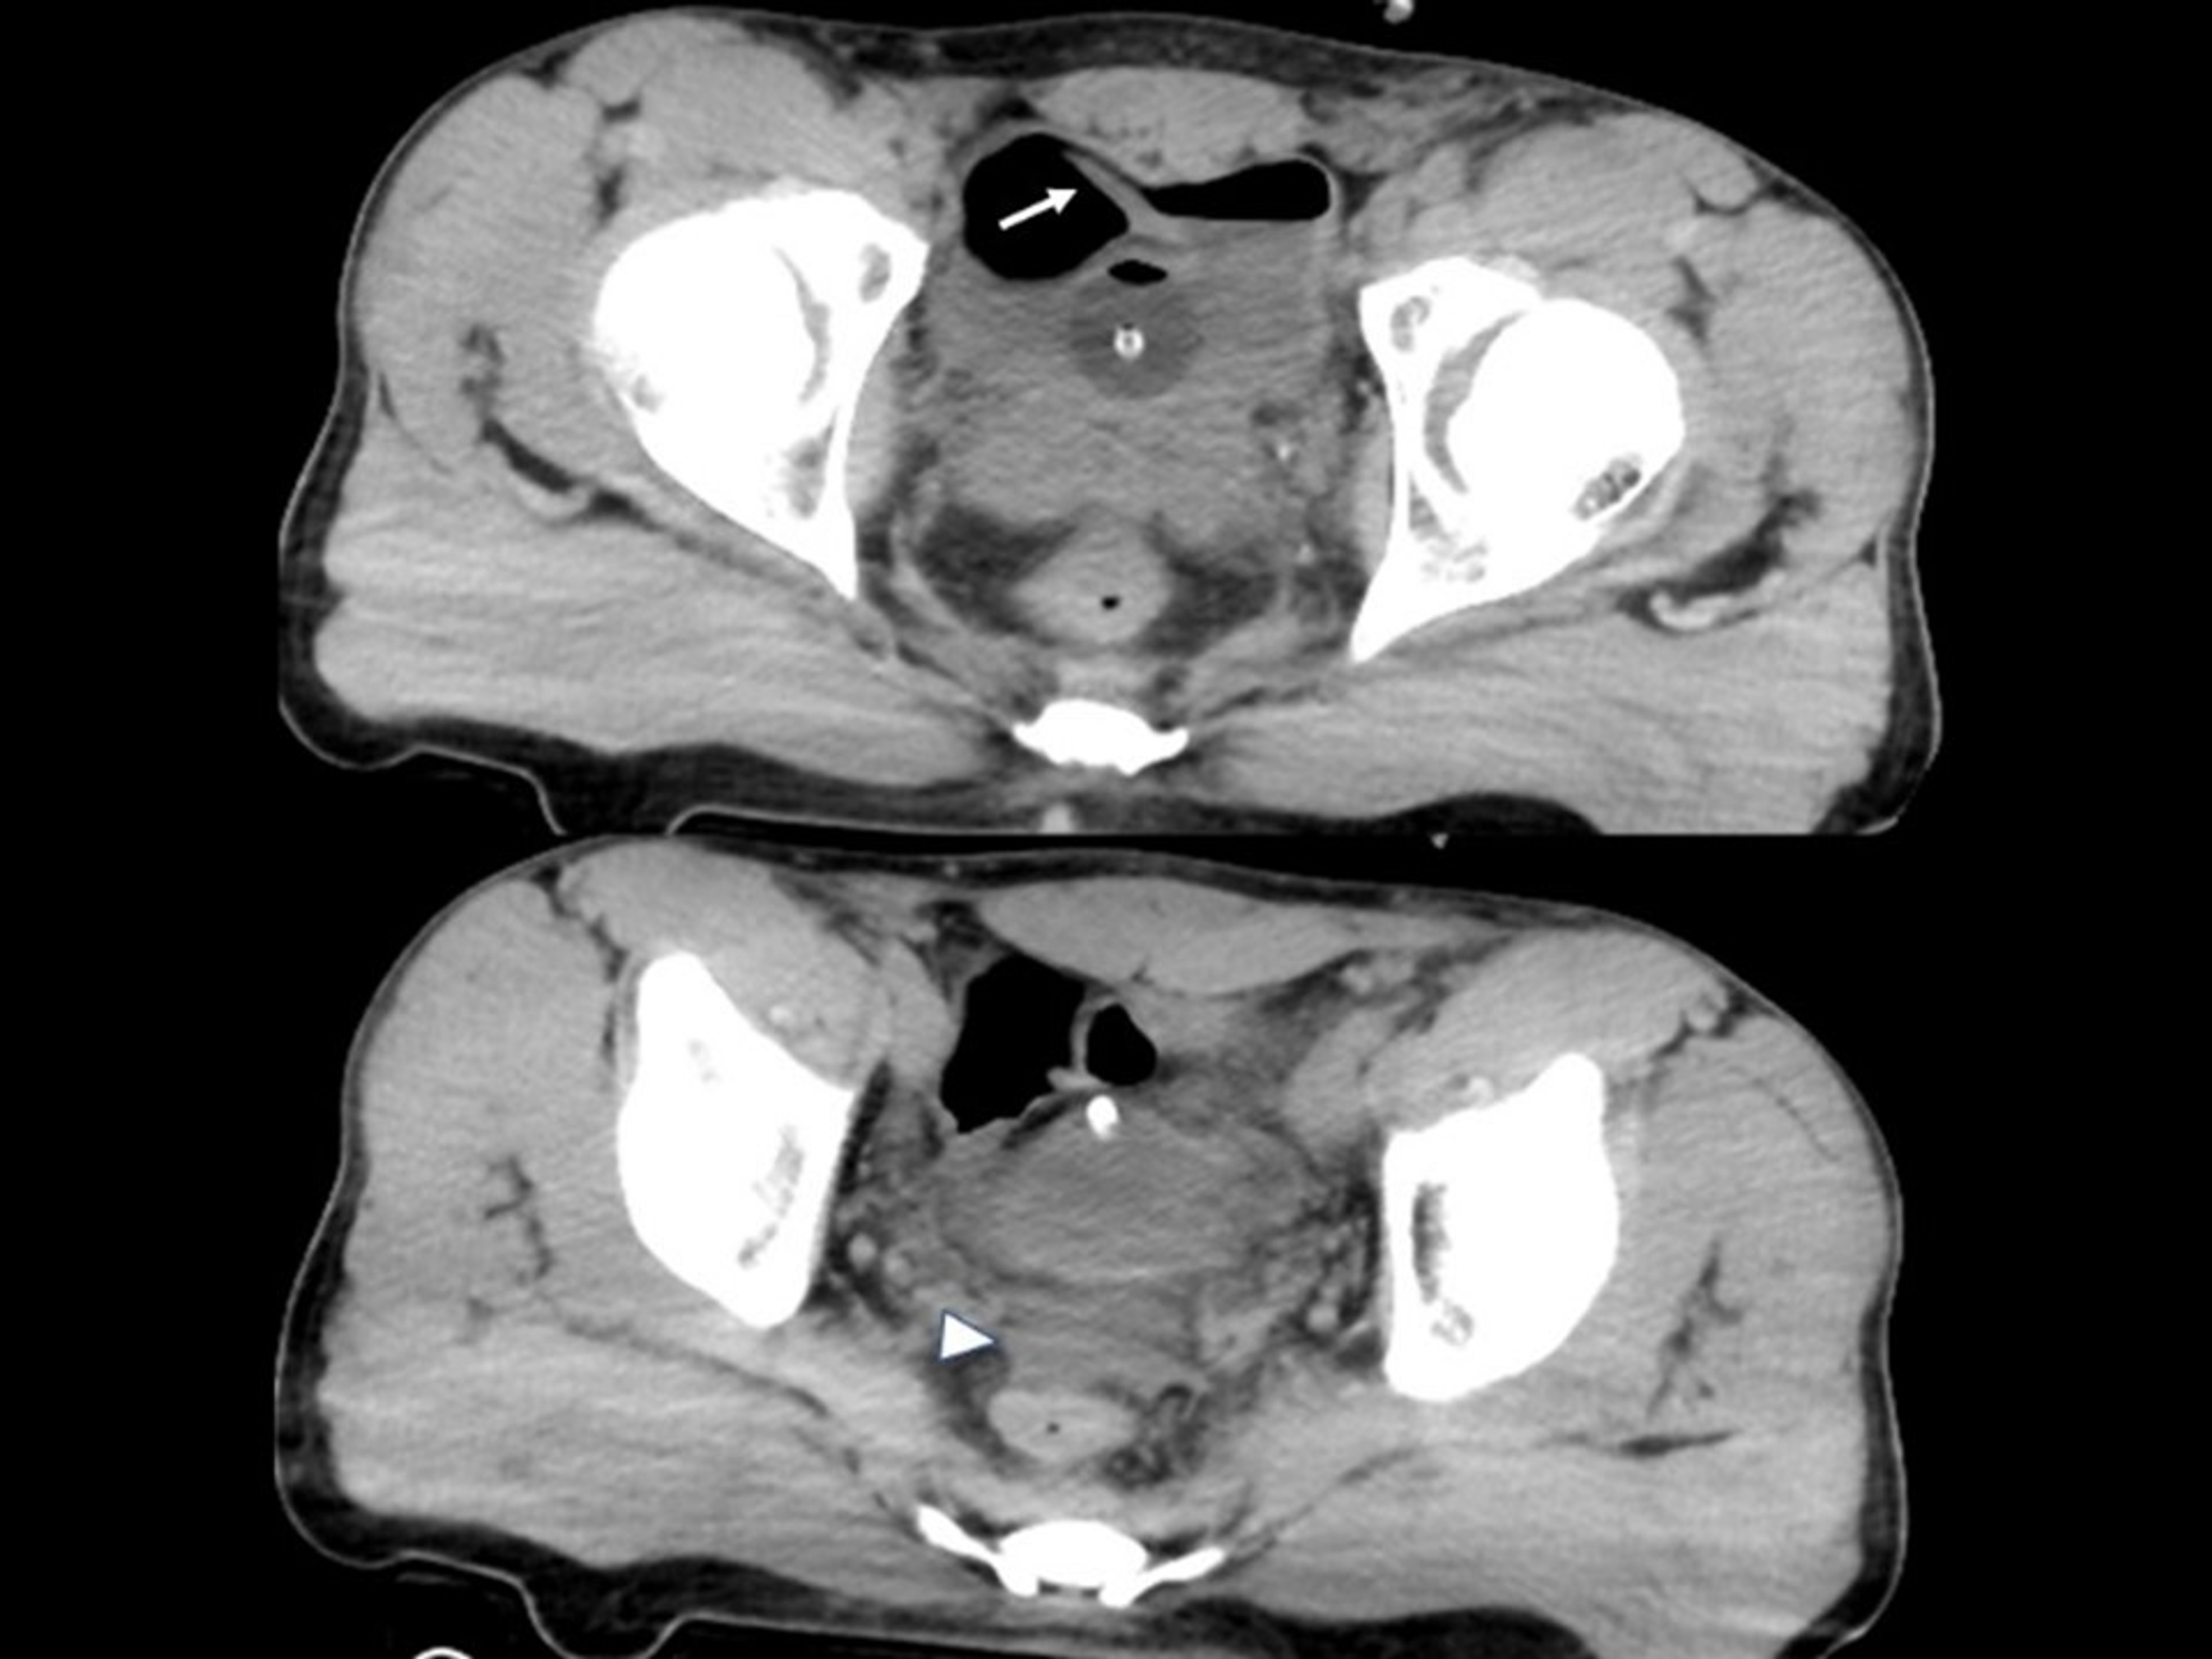

Figure 1 from Intraperitoneal urine leak following robotassisted laparoscopic radical

Intraperitoneal urine leak in a 68yearold patient with oliguria,... Download Scientific Diagram Intraperitoneal Bladder Leak Icd 10 Most extraperitoneal bladder leaks can be effectively managed with. — the most recent american urological association guidelines on urotrauma, updated in 2020, recommend that clinicians should perform catheter. — intraperitoneal bladder rupture. — bladder rupture is a relatively rare condition due to the protection of the bladder in the bony pelvis; Get free rules, notes, crosswalks, synonyms,. Intraperitoneal Bladder Leak Icd 10.